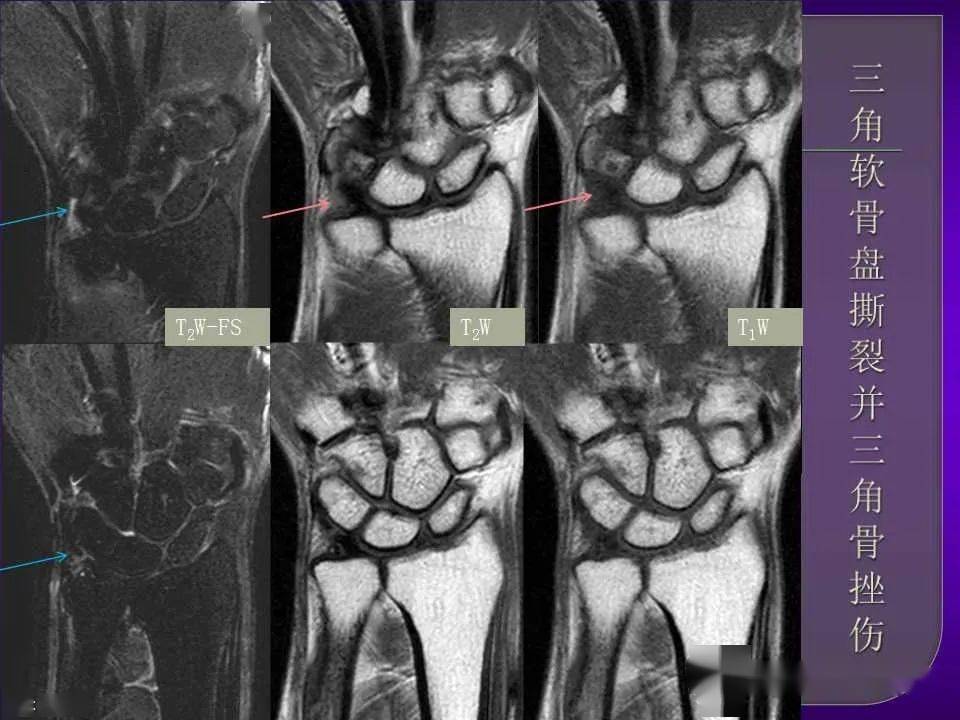

腕关节mri影像诊断ppt

腕肘关节损伤mrippt

影像基础腕关节损伤mri